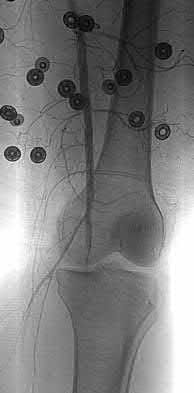

1010) Figures 66a through 66d are the radiographs and CT scans of a 72-year-old woman with osteoporosis who sustained a fall from standing height. She has pain and is unable to bear weight on the right knee. Surgical management is considered. Which of the following best describes the preferred proximal screw fixation construct within a laterally applied buttress plate?

5. 6.5-mm partially threaded cancellous screws Corrent answer: 2

Displaced split depression fractures of the lateral tibial plateau require articular surface elevation, restoration of anatomic plateau width, and sustained elevation of the reduced articular components. This is accomplished by introducing nonlocking lag screws first to compress and narrow the lateral rim thus restoring plateau width. The introduction of locking screws first would disallow compression and accordingly prevent reduction of the lateral rim.

Locking screws are inserted after the lag screws if the bone is osteoporotic to maintain articular elevation. Several biomechanical studies have demonstrated

inferior performance of large implants (6.5-mm screws and 4.5-mm plates) with regard to sustaining joint surface elevation.